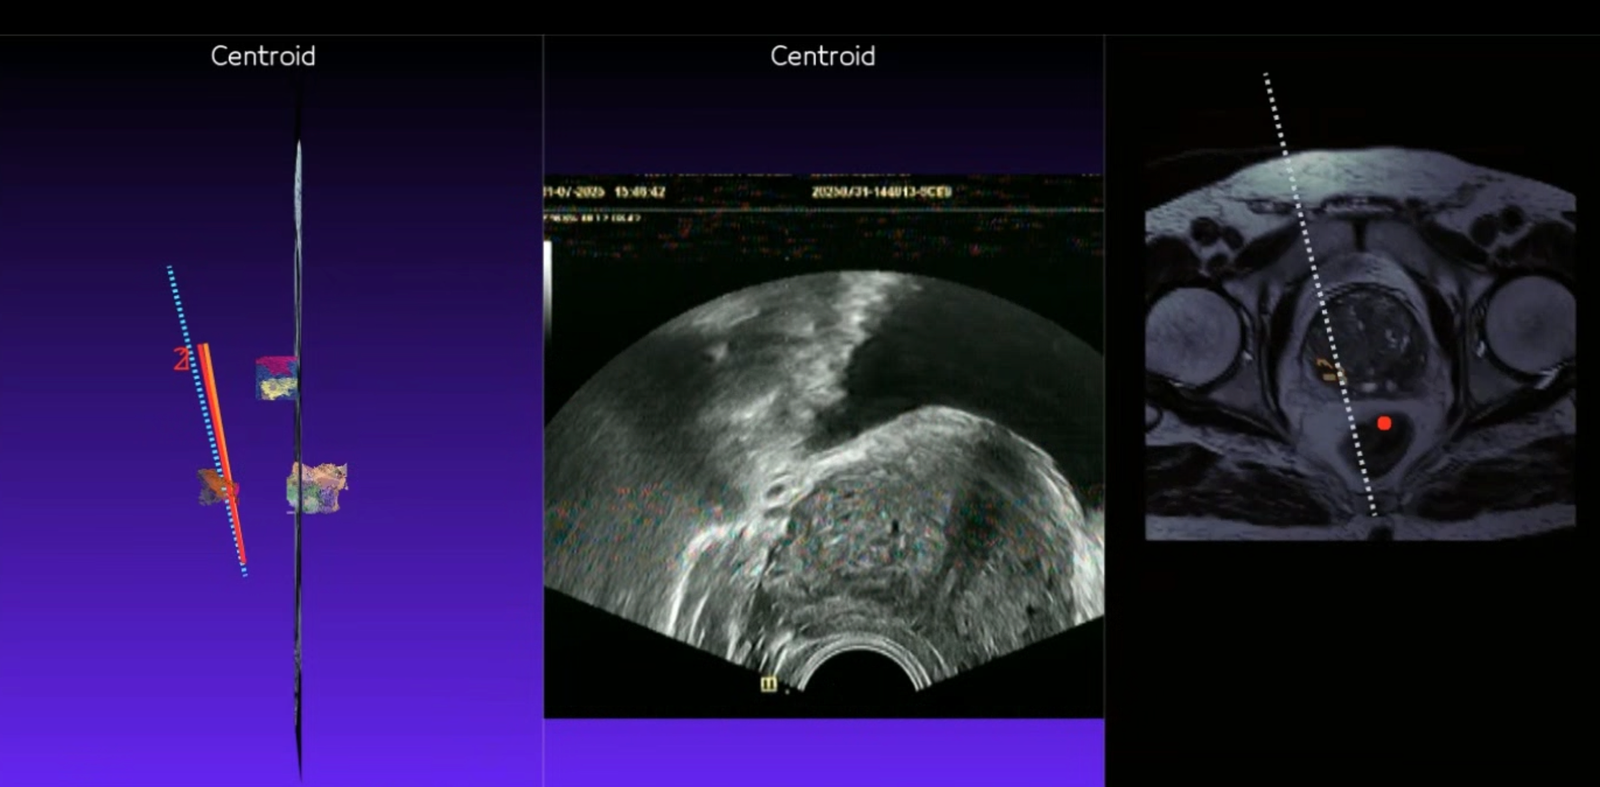

Prostat Füzyon Biyopsi

MR görüntüleri ile ultrason görüntülerinin birleştirilerek hedefe yönelik biyopsi yapılmasını sağlayan akıllı bir teknolojidir.

4. Adım: Füzyon ve Örnekleme

MR ve ultrason görüntüleri birleştirilir, **robotik sistemle** şüpheli hedeflerden hassas ve isabetli örnekler alınır.